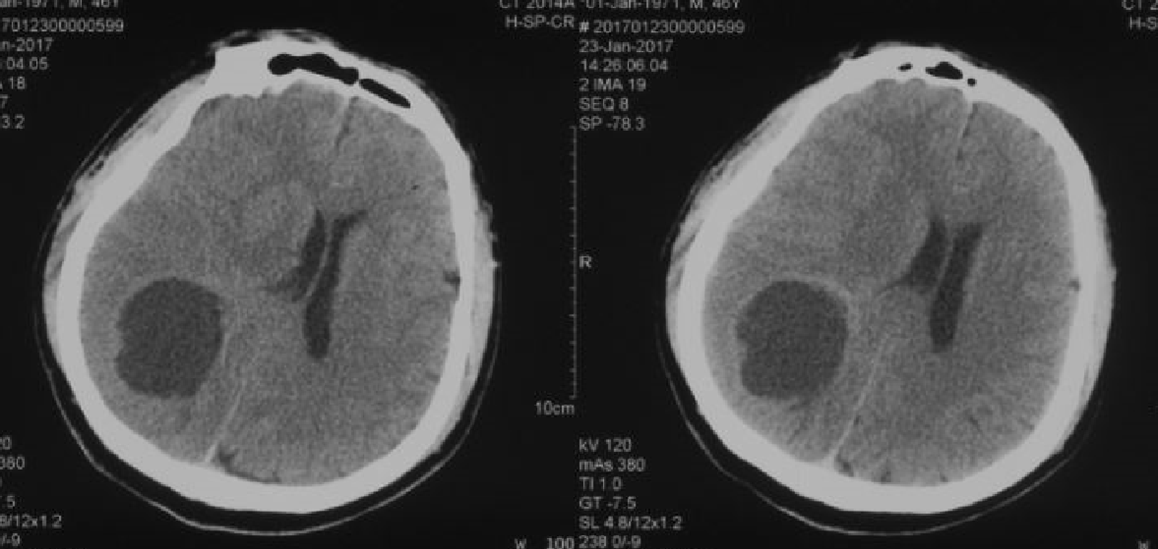

胶质瘤or转移瘤?

图片尺寸2048x1536